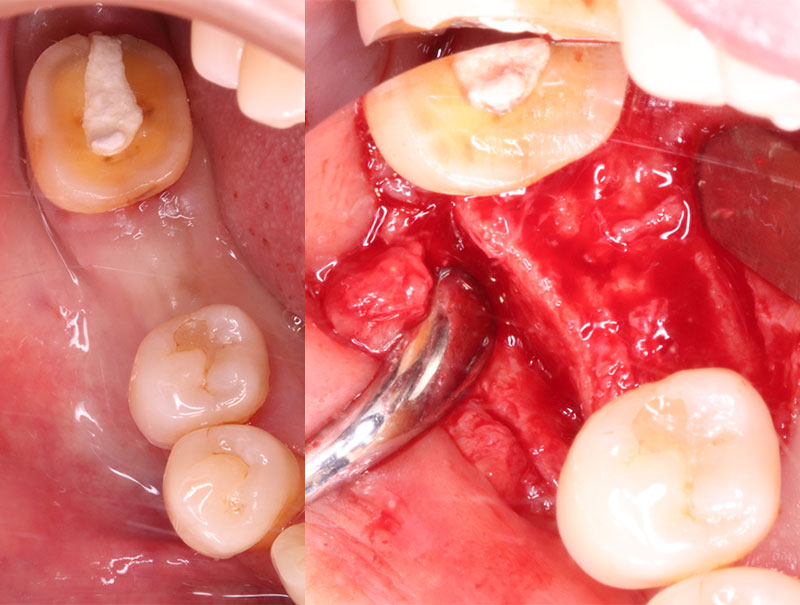

右下6の状態としては虫歯が進行していて、保存不可の状態でした。患者様との相談の結果、インプラント治療を行うことになりました。

残根抜歯とPRGFを使用した抜歯窩の保存

コラムを拝見してくださっている方は根っこだけだから簡単に抜歯できると思われがちかもしれませんが、そうはいきません。むしろ根っこだけの状態の方が抜歯は難しくなります。何故なら歯を抜く時に使用する鉗子(歯を引っ張って抜くためのペンチみたいな器具のこと)で掴むことが困難だからです。もし鉗子で掴むところがなければ根っこが埋まっている周囲の骨を削らないといけないです。周囲の骨を削ると抜歯後に骨が目減りするのでインプラントを行う際に不利になる可能性があるので、なるべく削らないようにします。このような時当院では図で示したような特殊な道具を使用します。この道具を使用して根っこを引っ張り出すように抜歯するので、周囲の骨を削る必要がありません。今回は特殊な道具を使用して抜歯できたのでよかったのですが、この道具を使用しても抜歯できない場合がありますので、その際は周囲の骨を削って抜歯するしかありません。

この道具なかなか高価なので持っている歯科医院さんが少ないのですが、自称抜歯専門としては持っておかなかればならないと思ったので思い切って購入しました。笑

またインプラント症例①でも行ったように抜歯窩の保存をするために、抜歯時にPRGFを抜歯窩に充填しました。